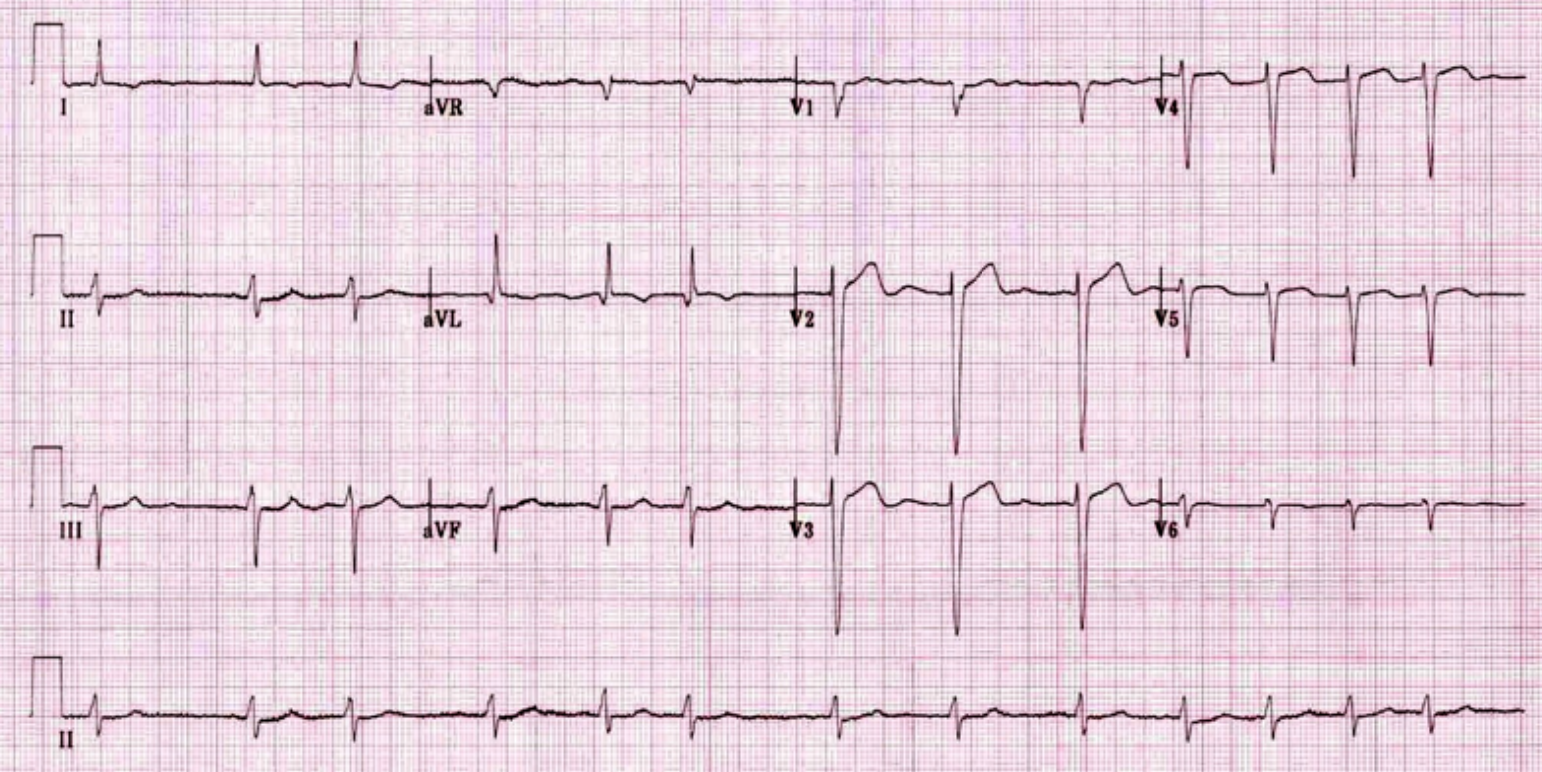

What abnormality do you see in this ECG? ST segment elevation in Lead 1, aVL, V2, V3, V4, V5 and V6

What is your clinical diagnosis? Anterolateral ST elevation Myocardial infarction (STEMI)

Mention 2 serum markers will you check to confirm your diagnosis? Troponin T and I, CK-MB

Mention 3 immediate treatment will you give to this patient? Supplemental O2, Morphine, Aspirin

Mention 3 risk factors for this condition? Hyperlipidemia, DM, Obesity, Smoking